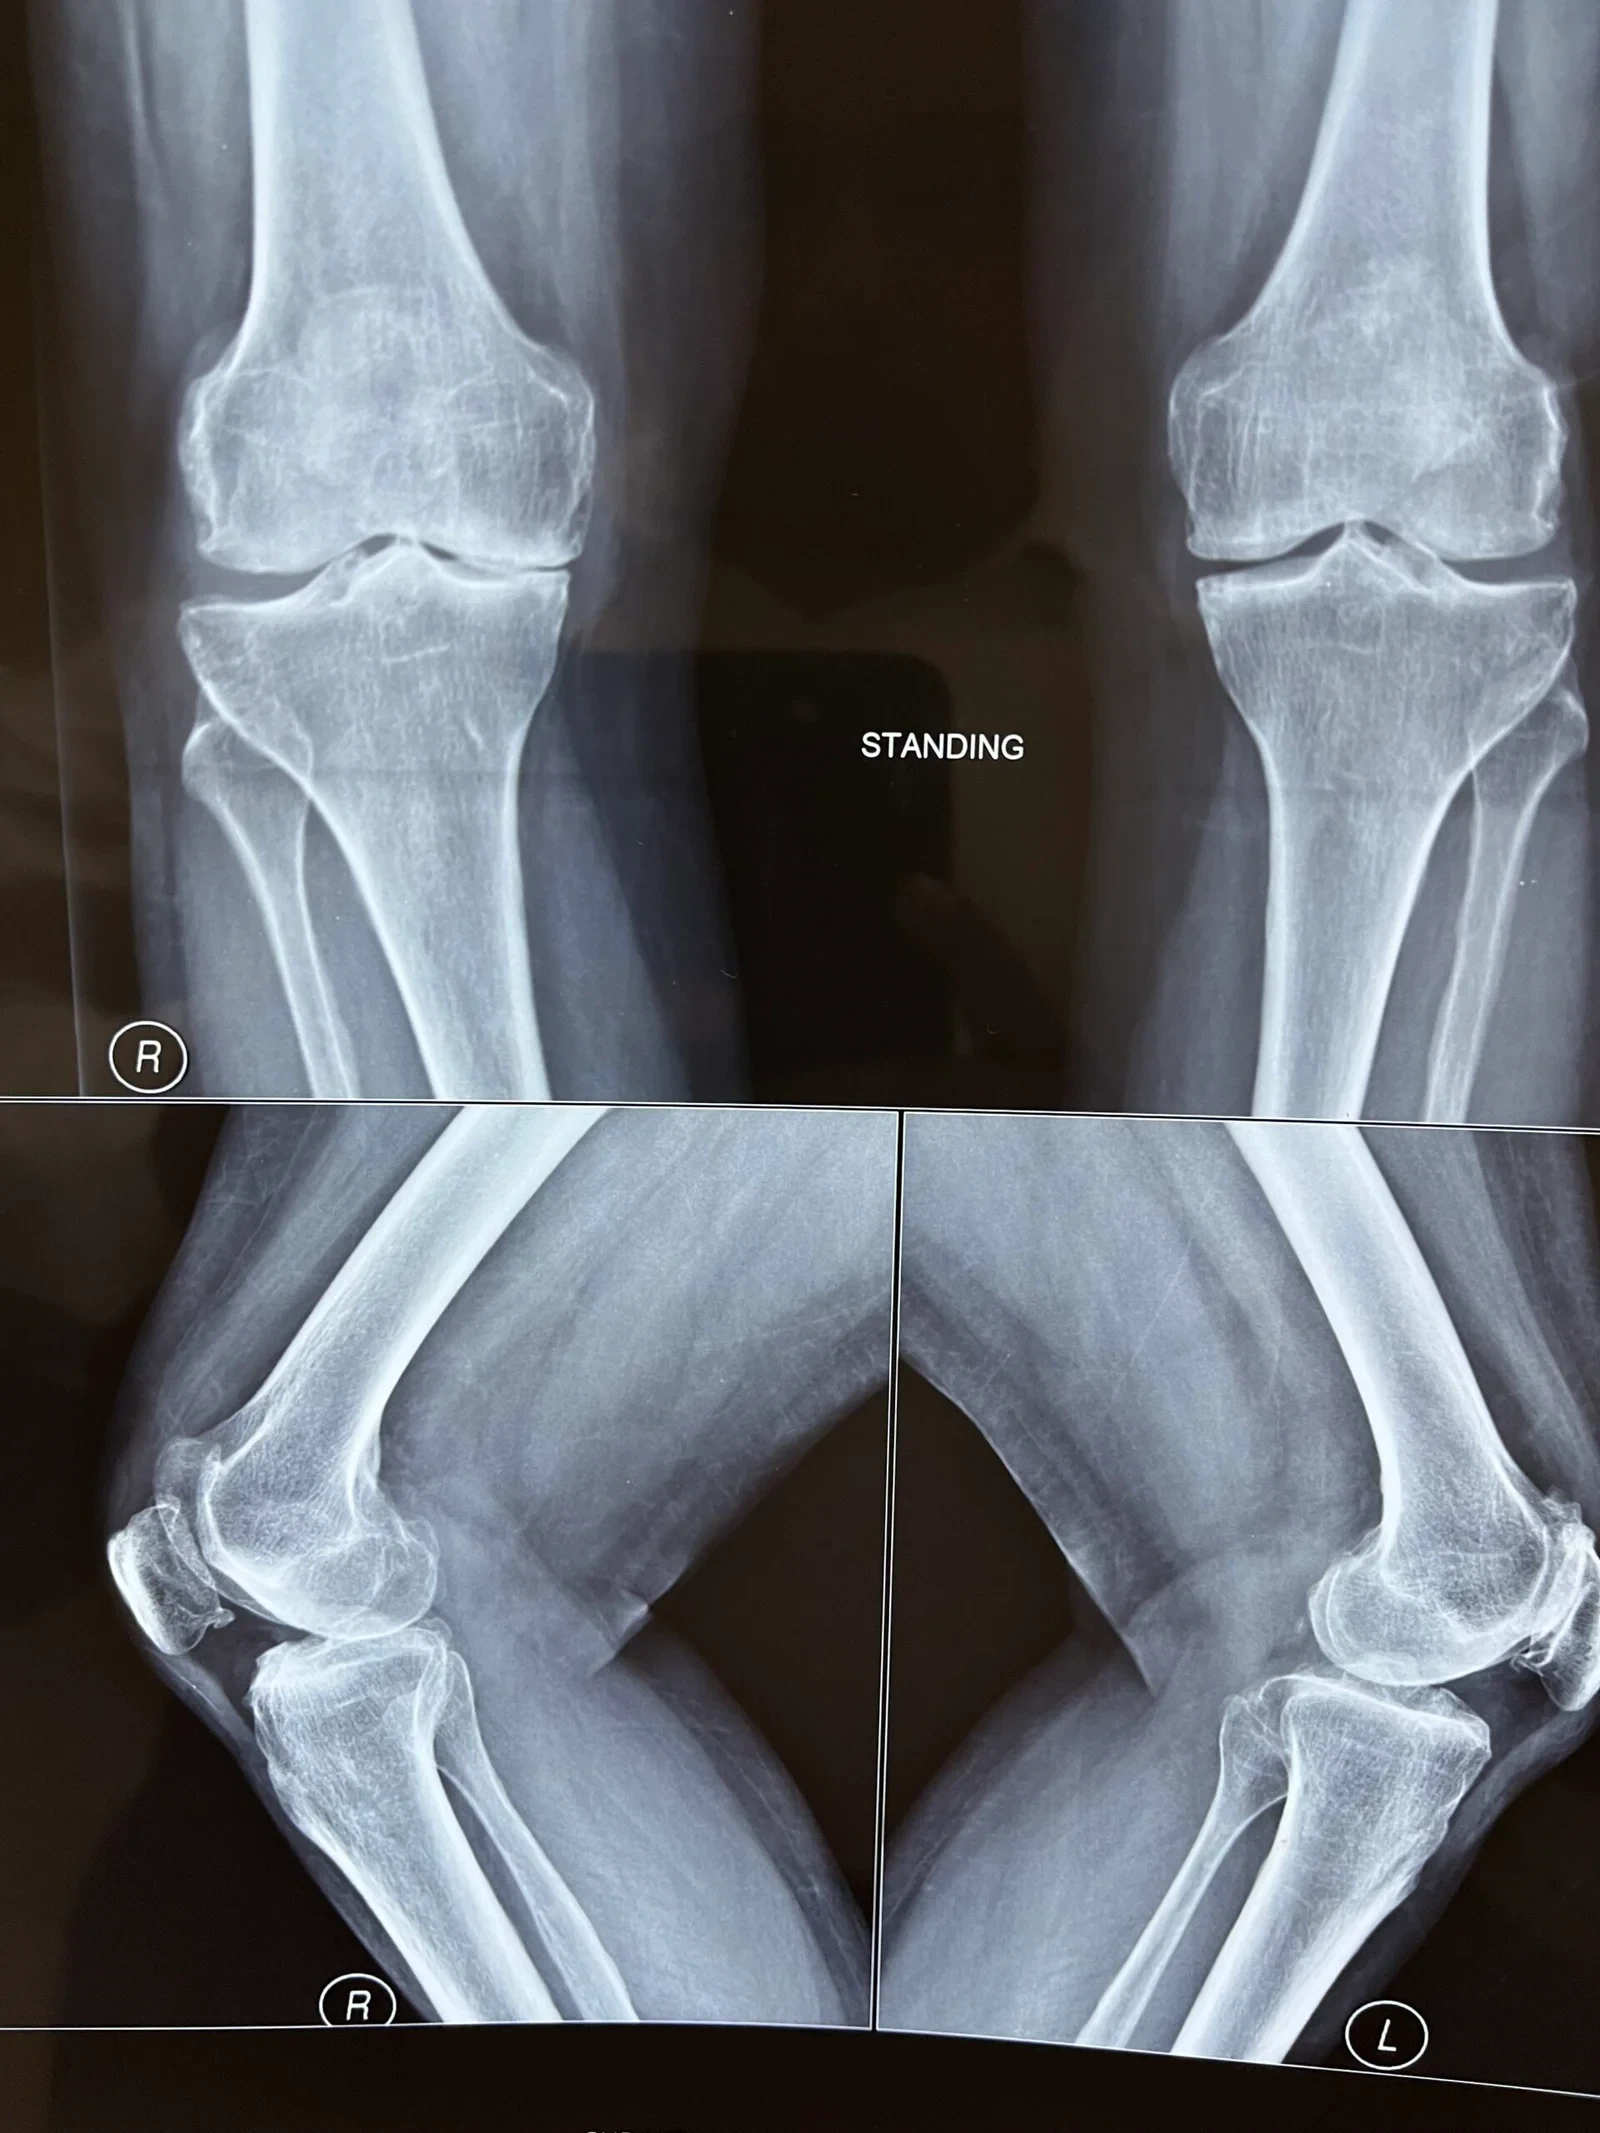

OA Knee with Correctable Varus Deformity

Pre-Op X-Ray